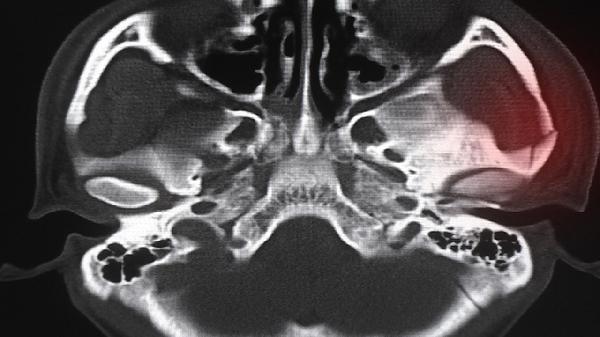

如果骨密度检测结果显示T值低于-2.5,或Z值低于-2并伴随骨折史,建议尽早就医。医生会根据具体情况制定个性化治疗方案,必要时进行骨代谢指标检测或影像学检查,进一步评估骨骼健康状况。